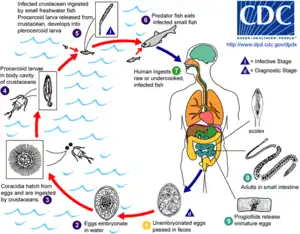

Adult tapeworms may infect humans, canids, felines, bears, pinnipeds, and mustelids, though the accuracy of the records for some of the nonhuman species is disputed. Immature eggs are passed in feces of the mammal host (the definitive host, where the worms reproduce). After ingestion by a suitable freshwater crustacean such as a copepod (the first intermediate host), the coracidia develop into procercoid larvae. Following ingestion of the copepod by a suitable second intermediate host, typically a minnow or other small freshwater fish, the procercoid larvae are released from the crustacean and migrate into the fish's flesh where they develop into a plerocercoid larvae (sparganum). The plerocercoid larvae are the infective stage for the definitive host (including humans).[6]

Because humans do not generally eat undercooked minnows and similar small freshwater fish, these do not represent an important source of infection. Nevertheless, these small second intermediate hosts can be eaten by larger predator species, for example trout, perch, walleye, and pike. In this case, the sparganum can migrate to the musculature of the larger predator fish and mammals can acquire the disease by eating these later intermediate infected host fish raw or undercooked. After ingestion of the infected fish, the plerocercoids develop into immature adults and then into mature adult tapeworms which will reside in the small intestine. The adults attach to the intestinal mucosa by means of the two bilateral grooves (bothria) of their scolices. The adults can reach more than 10 m (up to 30 ft) in length in some species such as D. latum, with more than 3,000 proglottids. One or several of the tape-like proglottid segments (hence the name tapeworm) regularly detach from the main body of the worm and release immature eggs in freshwater to start the cycle over again. Immature eggs are discharged from the proglottids (up to 1,000,000 eggs per day per worm) and are passed in the feces. The incubation period in humans, after which eggs begin to appear in the feces is typically 4–6 weeks, but can vary from as short as 2 weeks to as long as 2 years.[7]